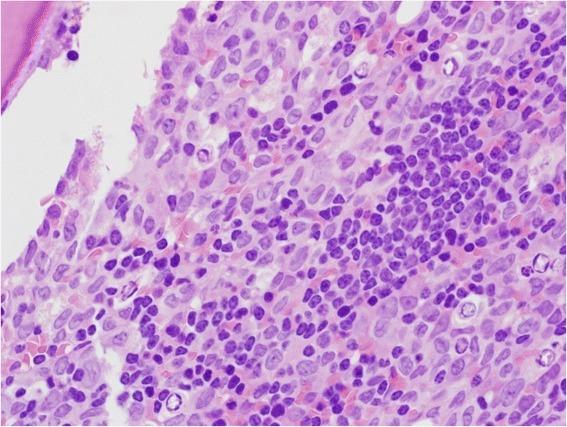

We describe a case of a 77-year-old man who presented with fatigue, pallor and lower limb pain and weakness. Initial laboratory studies showed Hb 7.7 g/dl, WBC 279.6 × 10(9)/1, PLT 143× 10(9)/1. The peripheral blood (PB) smear examination showed circulating blast cells (20 %) cells and 50 % lymphocytes, with smudge cells. A bone marrow examination showed infiltration by two discrete abnormal cell populations, one represents the leukemic blast cells (60 %) and the other represents small mature lymphocytes (30 %). The immunologic phenotype of blasts was characterized by the co-expression of CD13, CD33, CD14, CD4, CD15, CD64, HLA-DR, CD11c. Lymphocytes were characterized by a typical CLL immunophenotype: CD19+, CD5+, CD23+, CD20+ (dim) and negative for FMC7, CD34, CD10 and TdT. Cytogenetic studies were negative for CLL and AML panels. PCR assays for AML specific genetic abnormalities were negative. Immunoglobulin gene analysis established the clonal nature of the B-cell expansion. A final diagnosis of concomitant CLL and AML(FAB: M5) was made.

我们描述了一名77岁男性患者,其表现为疲劳、面色苍白以及下肢疼痛和无力。初始实验室检查显示血红蛋白(Hb)7.7 g/dl,白细胞(WBC)279.6×10⁹/L,血小板(PLT)143×10⁹/L。外周血涂片检查显示循环中的原始细胞(20%)和50%的淋巴细胞,伴有涂抹细胞。骨髓检查显示有两种离散的异常细胞群浸润,一种代表白血病原始细胞(60%),另一种代表小成熟淋巴细胞(30%)。原始细胞的免疫表型特征为CD13、CD33、CD14、CD4、CD15、CD64、HLA - DR、CD11c共表达。淋巴细胞具有典型的CLL免疫表型:CD19⁺、CD5⁺、CD23⁺、CD20⁺(弱阳性),FMC7、CD34、CD10和TdT为阴性。细胞遗传学研究对CLL和AML检测均为阴性。AML特异性基因异常的聚合酶链反应(PCR)检测为阴性。免疫球蛋白基因分析确定了B细胞扩增的克隆性质。最终诊断为CLL与AML(FAB:M5)同时存在。